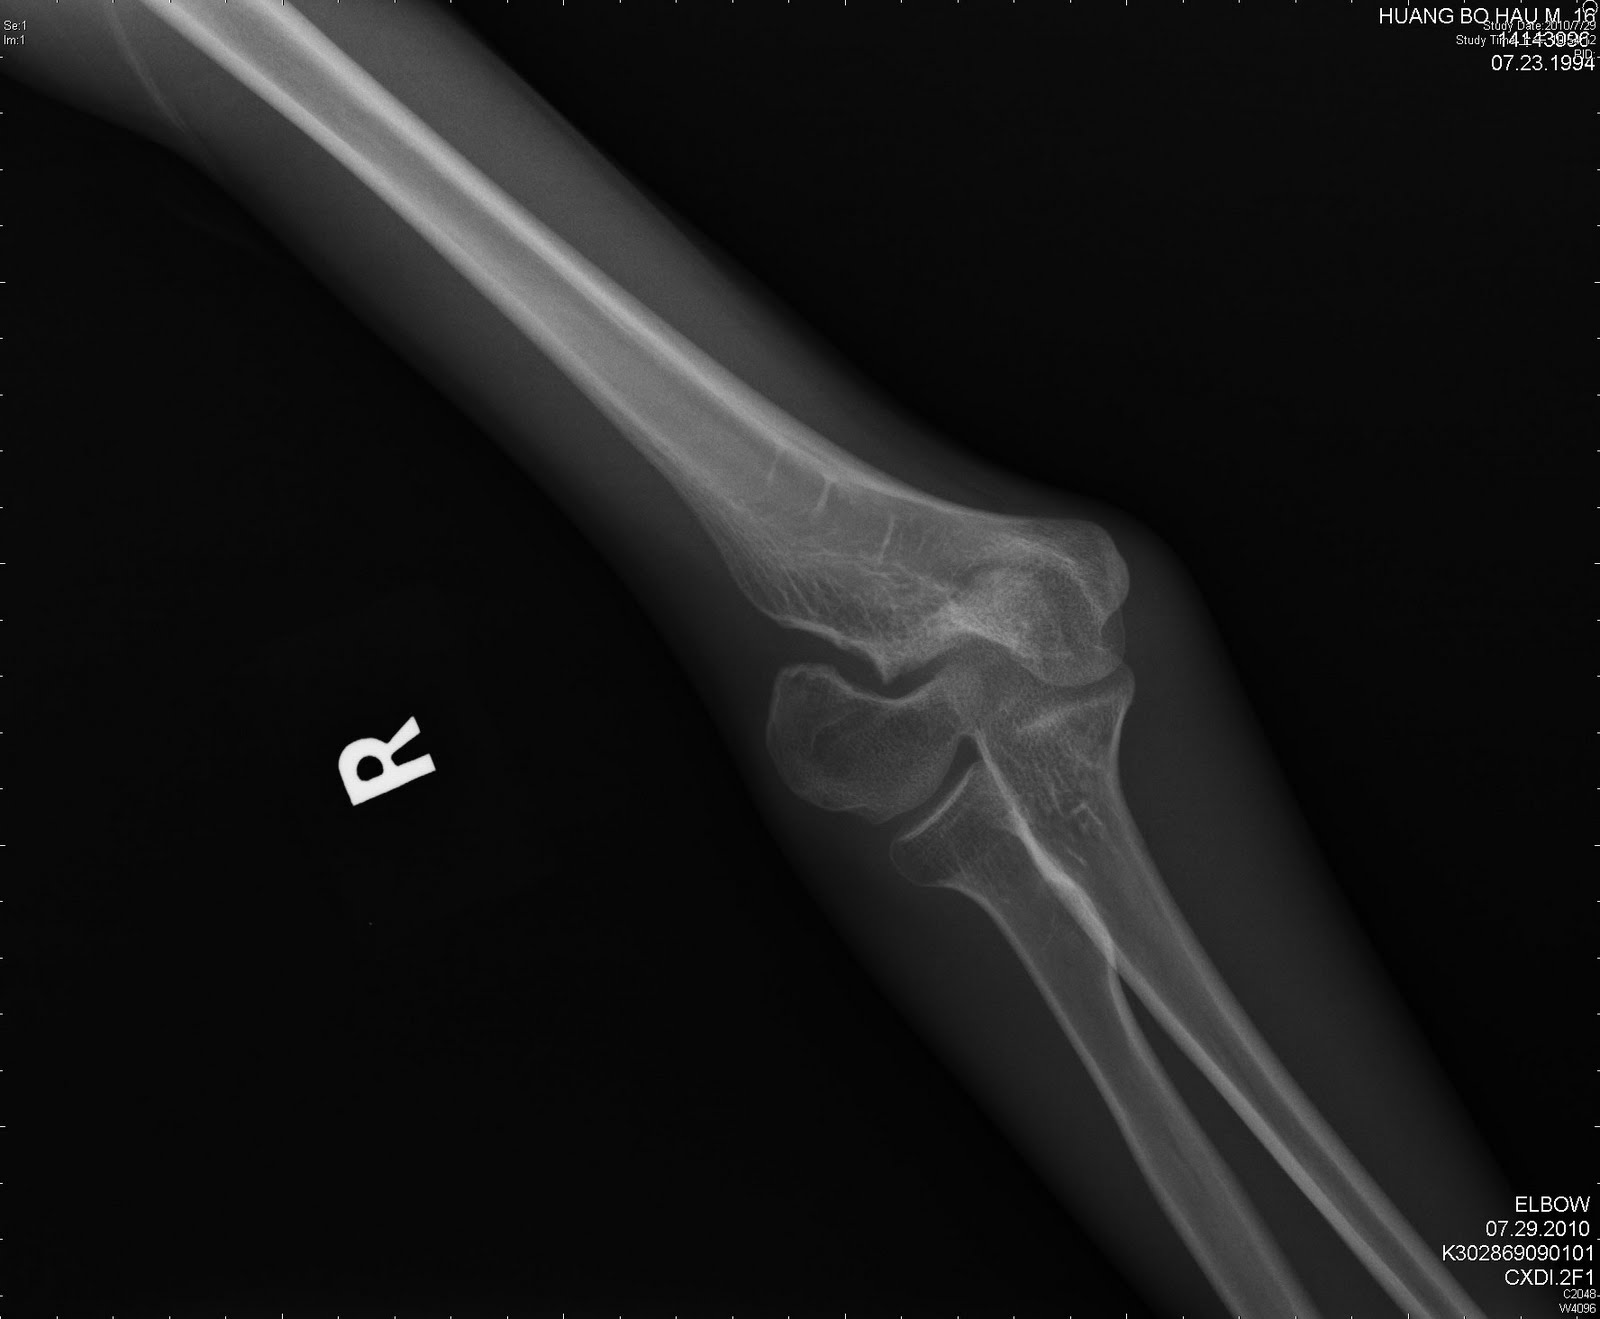

Fracture of neck of femur transcervical fracture, closed transcervical fracture, open pertrochanteric fracture complication unilateral, at or above elbow, complicated unilateral, level not specified, without mention of. Are all elbow pain icd 9 code valid to use? The following is a list of codes for international statistical classification of diseases and related health problems. Use of valid icd9 codes, billed with appropriate and corresponding in addition, to remain consistent with the icd9 cm official guidelines for coding and reporting elbow and forearm sprains and strains of wrist, unspecified site sprains and strains of carpal (joint) sprains. Lateral femoral condyle compression fracture icd 9. Fracture pain down back of leg; Wrist, carpal tunnel syndrome wrist, sprain / strain. Billable medical code for closed fracture of unspecified part of femur. To code a diagnosis of this type, you must use one of the nine child codes of s82 that describes the diagnosis 'fracture of lower leg, including ankle' in more detail. A femur fracture is a break in the femur bone of the thigh. Learn vocabulary, terms and more with flashcards, games and other study tools. Left elbow fracture icd 10 code icd 10 code for right elbow infection. The above description is abbreviated. Any cut, fracture, burn or scrape gives bacteria an entry point. prion disease + major neurocognitive disorder due to prion disease, without behavioral disturbance. These deal offers are from many sources. Injuries are classified first according to the general type of.